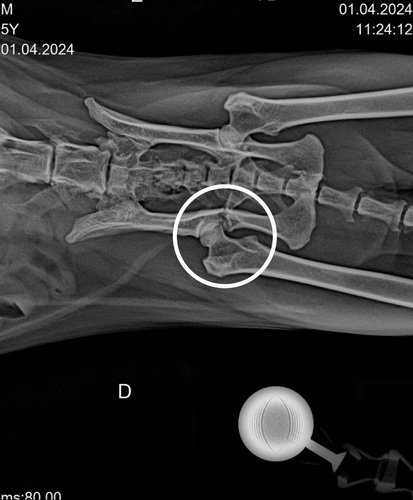

Cirurgia de Colocefalectomia no Fêmur Direito

Bom dia, Me Chamo Rosania, estou realizando uma vakinha no valor de R$ 2000,00 pra arcar com os custos de uma cirurgia do colocefalectomia no fêmur direito para um gatinho de rua que foi atropelado, minha filha o resgatou e estamos acompanhando a situação os documentos estão no nome dela, criei a vakinha para ajudar na cirurgia.Estamos dando um lar temporario para ele no momento deixando ele o mais confortavel possivel, ele está com a coleira pois ele tenta fugir o tempo todo pra rua, estamos arcando com os remédios e a consulta, ele também está com Esporotricose que estamos tratando com medicação, porém a cirurgia é mais do que eu posso fornecer sozinha no momento para ajudá-lo. Conto com a sua ajuda. Deus abençoe.